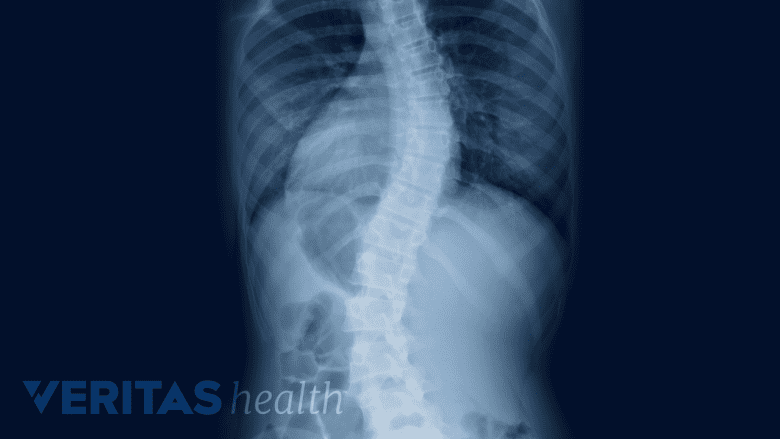

• Spinal alignment disorders (abnormal curves of the spine), such as scoliosis or kyphosis

A full-length spinal x-ray series, also known as a “scoliosis series,” is taken while standing. The series provides important postural data, such as segmental and total angles of curvature between the vertebrae, balance, and degenerative processes.

See Cobb Angle Used to Measure Scoliosis Curves